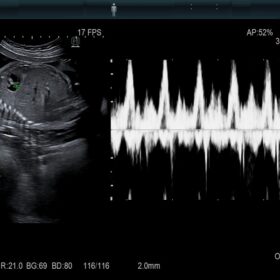

Radiology

Be prepared for various clinical cases.

- Highly sensitive B-mode and Color Mode

- Advanced Elastography features

Women’s Health

Be equipped for breast pathologies and fetal assessment.

- Highly sensitive colour mode to replace contrast agents

- Doppler measurements from two gates in same heart cycle

- Advanced vessel and blood flow analysis tools